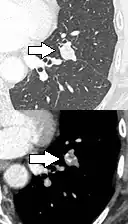

- Location: Upper lobe location is a risk factor for cancer, while a location close to a fissure or the pleura indicates a benign lymph node,[8] especially if having a triangular shape.[9]

- Margin morphology: a spiculated margin is a risk factor for cancer.[8] Benign causes tend to have a well defined border, whereas lobulated lesions or those with an irregular margin extending into the neighbouring tissue tend to be malignant.[10] In particular, spiculations are highly predictive of malignancy with a positive predictive value up to 90%.[9] Also, a "notch sign", which is an abrupt indentation of the nodule, increases the risk of cancer, but may also be found in granulomatous diseases.[9]

subpleural nodule.[9] -

A triangular perifissural node can be diagnosed as a benign lymph node.[9]